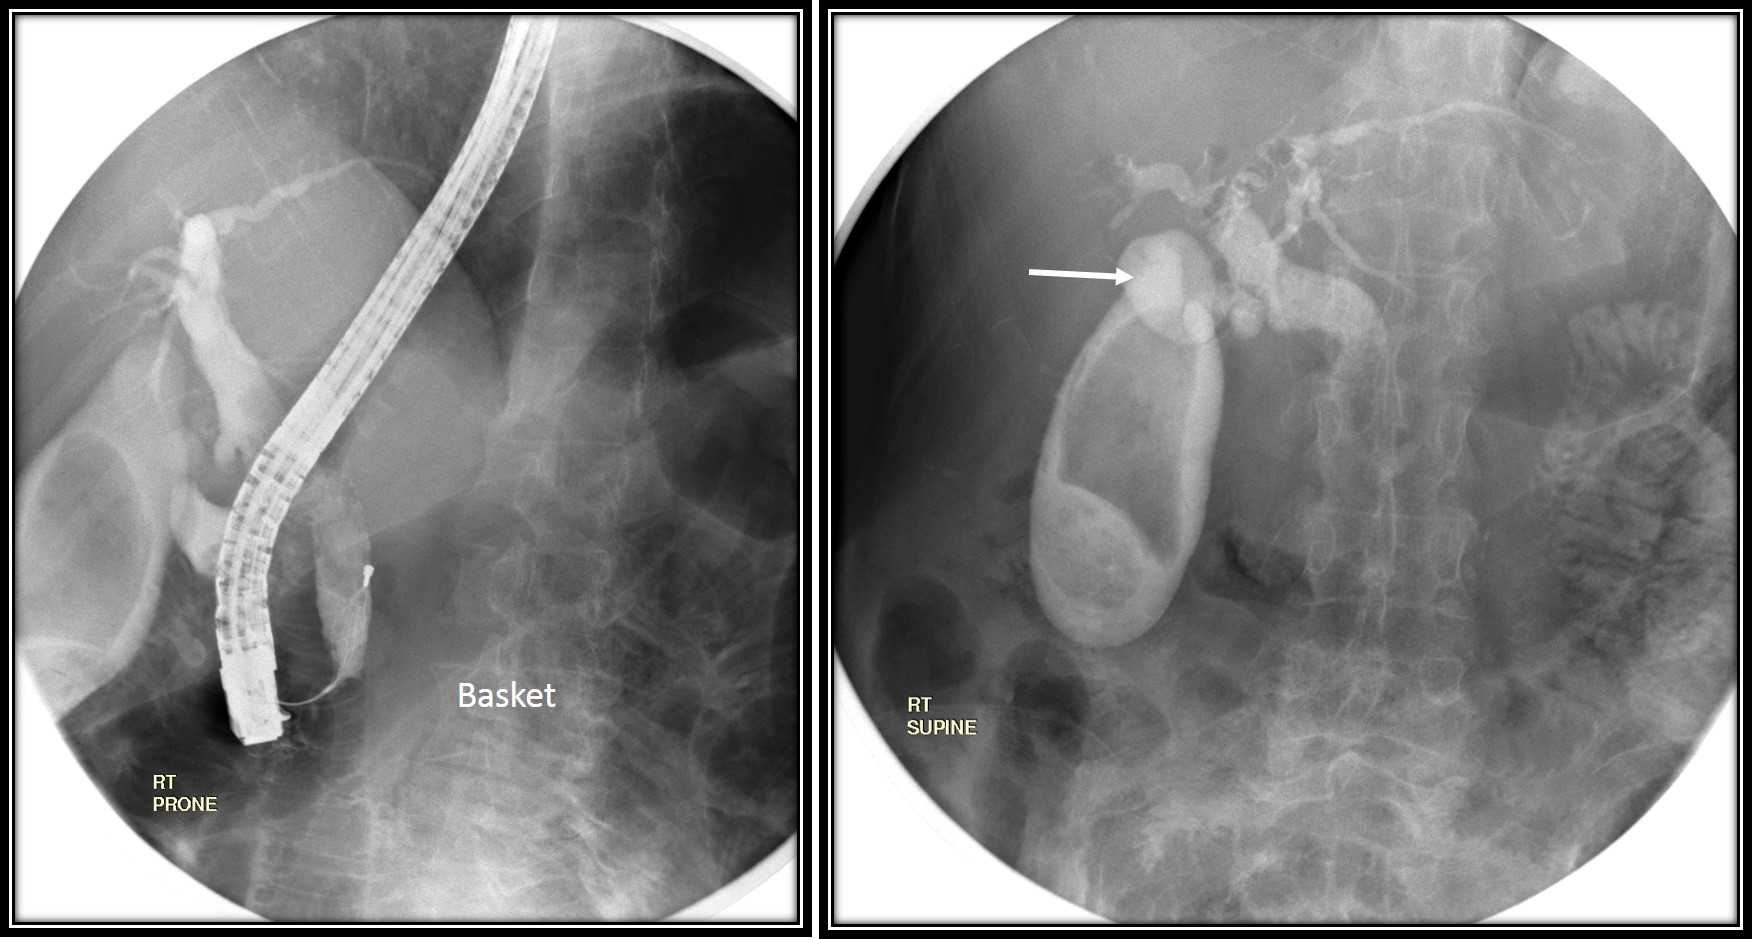

From radiologycases.my

Endoscopic removal of choledocholithiasis Radiology Cases Endoscopy For Cholelithiasis endoscopic retrograde cholangiopancreatography (ercp) is an invasive procedure used for the diagnosis and treatment of obstruction in the biliary system. gallstones (cholelithiasis) are hardened pieces of bile that form in your gallbladder or bile ducts. endoscopic retrograde cholangiopancreatography, or ercp, is a procedure to diagnose and treat problems in the liver, gallbladder, bile ducts, and pancreas. It. Endoscopy For Cholelithiasis.

Endoscopic removal of choledocholithiasis Radiology Cases Endoscopy For Cholelithiasis It is used to diagnose and. endoscopic retrograde cholangiopancreatography, or ercp, is a procedure to diagnose and treat problems in the liver, gallbladder, bile ducts, and pancreas. during endoscopic ultrasound (eus) your doctor passes a thin, flexible tube (endoscope) through your mouth and through. endoscopic retrograde cholangiopancreatography (ercp) is an invasive procedure used for the diagnosis and. Endoscopy For Cholelithiasis.